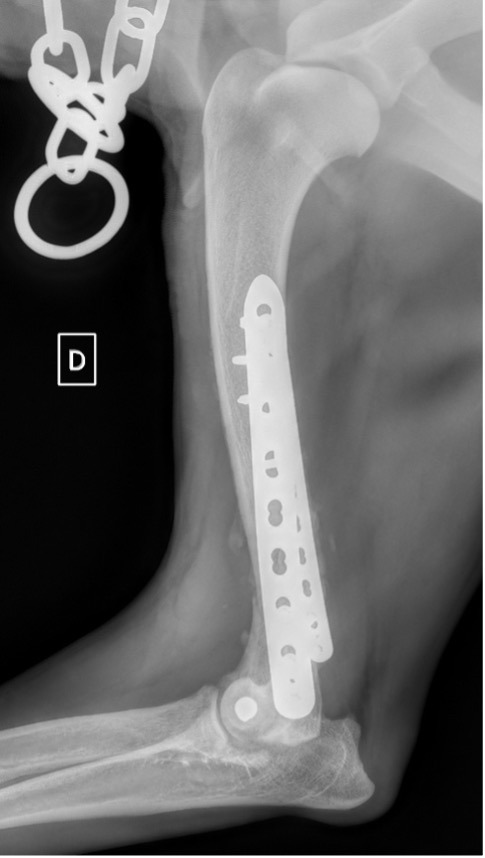

L’avènement récent des plaques anatomiques constitue une nouvelle option dans le traitement de ces fractures : dans l’exemple 3 (chat Ragdoll), une plaque anatomique médiale de 2 mm acceptant des vis de 1,6 et 2 mm a été utilisée seule avec succès.

Figure 9 : Pré-Op

Figure 10 : Opération

Figure 11 : Post-Op Immédiat

Figure 12 : Post-Op 1 mois